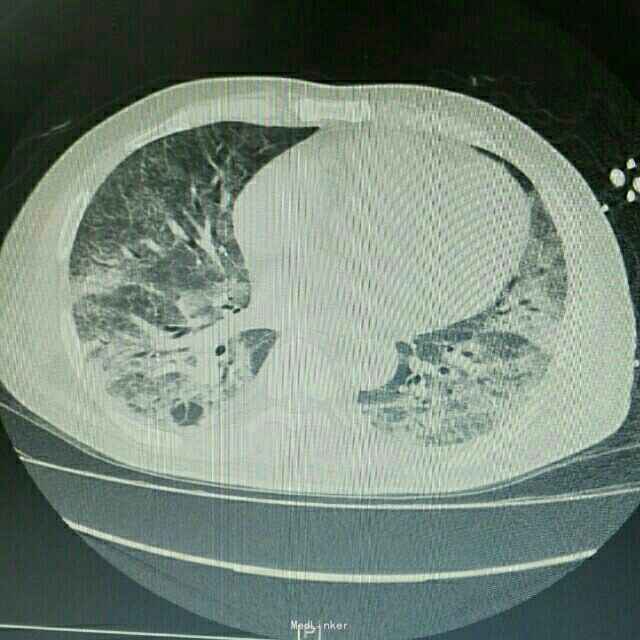

主诉:肾移植术后2月,发热、咳嗽5天 病史:患者男,45岁,因尿毒症于2月前在外院行异体肾移植术,手术过程顺利,术后恢复良好,移植肾功能稳定,服用FK506+MMF+Pred免疫抑制维持治疗。患者术后未规律门诊随诊,有情况变化时常电话联系行手术的医院,在术后免疫抑制剂服用剂量较大,为MMF1gBid+FK506 3.5mgBid+Pred25mgQd,其中FK506平时维持的浓度约10ng/ml。5天前开始出现发烧,最高体温38.8℃,自服“降温药”后体温可下降,伴咳嗽,无胸闷气促,无诉其他不适。

辅助检查:患者入院后症状进行性加重,入院2日后出现胸闷、气促,动脉血气分析提示氧分压为59mmHg,胸部CT提示双肺严重弥漫性炎症。

诊断:肺部感染;异体肾移植状态 治疗:患者入院后积极抗感染治疗,检查胸部CT和血气分析后给予吸氧等对症治疗,抗感染方案为泰能+伏立康唑+科赛斯+更昔洛韦,并停用所有口服免疫抑制剂,改为甲强龙40mgQd静脉滴注,患者治疗后肺部感染无明显好转,2日后转入ICU进一步治疗。